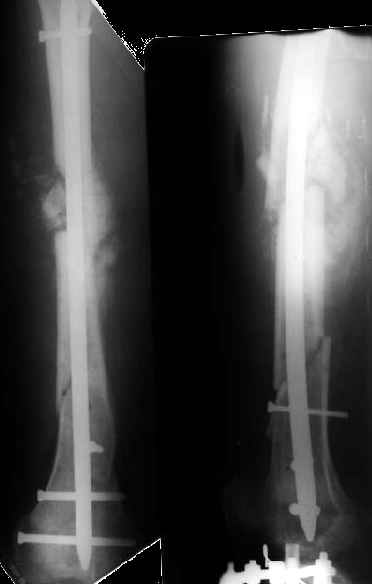

Как я уже сообщал, пациент поступил к нам в пятницу на прошлой неделе.

Сегодня сделана операция. Из бедра минимально инвазивно удалены пластинки. Один винт на верхней пластинке оказался сломан, так что пришлось там сделать разрезик побольше, см 5.

Хотя и с трудом, но на бедре удалось сразу выполнить закрытый интрамедуллярный остеосинтез с минимальным рассверливанием.

На голени - чрескожная остеотомия малоберцовой кости, закрытая остеоклазия большеберцовой, дистракционный остеосинтез аппаратом.

В плане - востановление длины и оси голени, разработка движеий в колене. Не уверен, что удастся синтезировать голень стержнем при таком маленьком сгибании в коленном суставе.